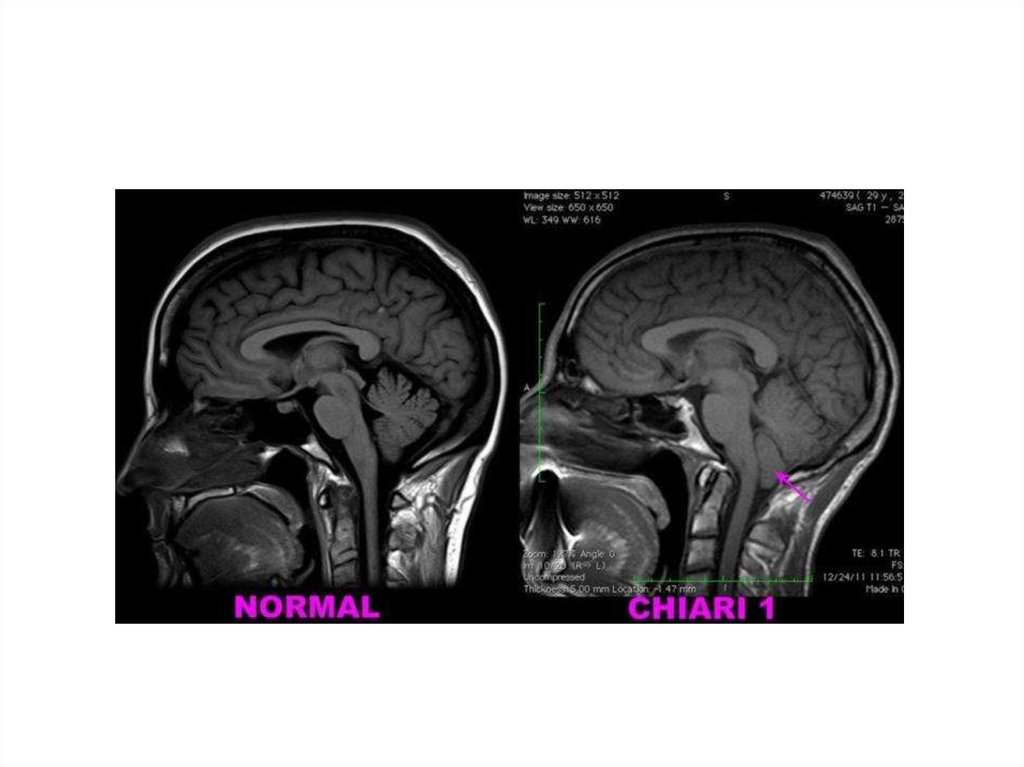

32. Мальформация Арнольда-Киари

https://commons.wikimedia.org/wiki/File:Chiari2.jpg?uselang=ru

33.

34.